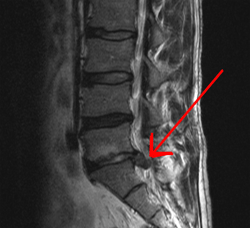

الأسباب المباشرة يمكن أن تشمل هشاشة العظام، روماتيزم ،التهاب المفاصل، أرثرتس، وتآكل للأقراص بين فقرات، أو فتق في قرص العمود الفقري (انزلاق غضروفي)، انكسار الفقري (مثل ترقق العظام)، أو نادرا التهاب أو ورم (بما في ذلك السرطان). وقد يكون السبب أيضا نفسي أو عاطفي أو إلى أسباب أخرى غير العوامل التشريحية.

- فتق القرص الفقري (انزلاق غضروفي).

التشخيص الكامل عادة من خلال مزيج من التاريخ الطبي للمريض، والفحص البدني، وعند الاقتضاء، الاختبارات التشخيصية، مثل أشعة الرنين المغناطيسي أو الأشعة السينية.